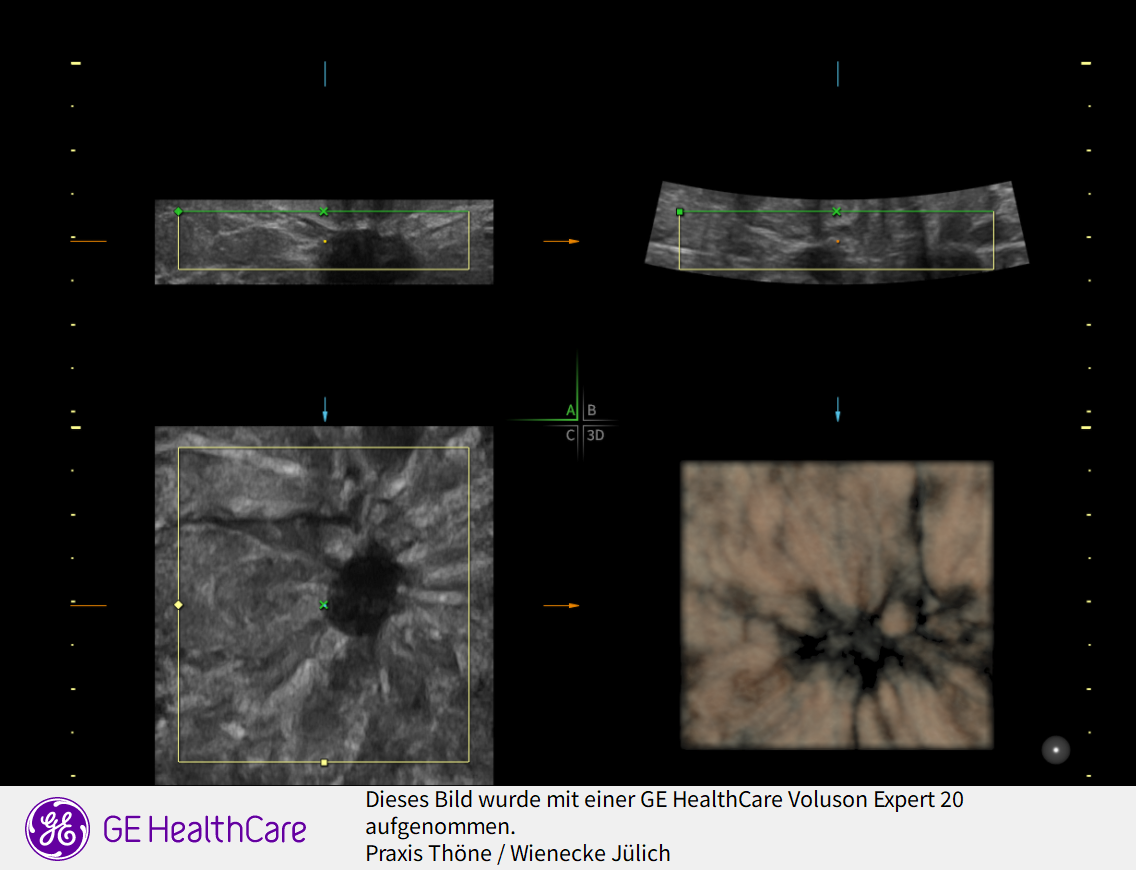

3D Sonographie der Brustdrüse

Was ist der Unterschied zur normalen Sonographie?

Der Ultraschall ist eine Untersuchung ohne Strahlenbelastung. In unsrer Praxis werden hochauflösende Ultraschallköpfe verwendet, die eine hohe Genauigkeit und sehr gute Auflösung ermöglichen. D.h. auch kleinste Veranderungen können schon gesehen werden. Mit der 3 D Sonographie können Veränderungen des Gewebes in ihrer Abgrenzung zum normalen umgebenden Gewebe besser beurteilt werden als nur mit der 2 D Methode. Bösartige Knoten bilden Ausläufer in das umgebende Gewebe, die wie kleine Strahlen einwachsen. Diese Phämomene können mit der 3 D Sonographie beurteilt werden, die Unterscheidung zwischen gutartigen und bösartigen Veränderungen wird genauer und die Rate an unnötigen Biopsien kann vermindert werden.